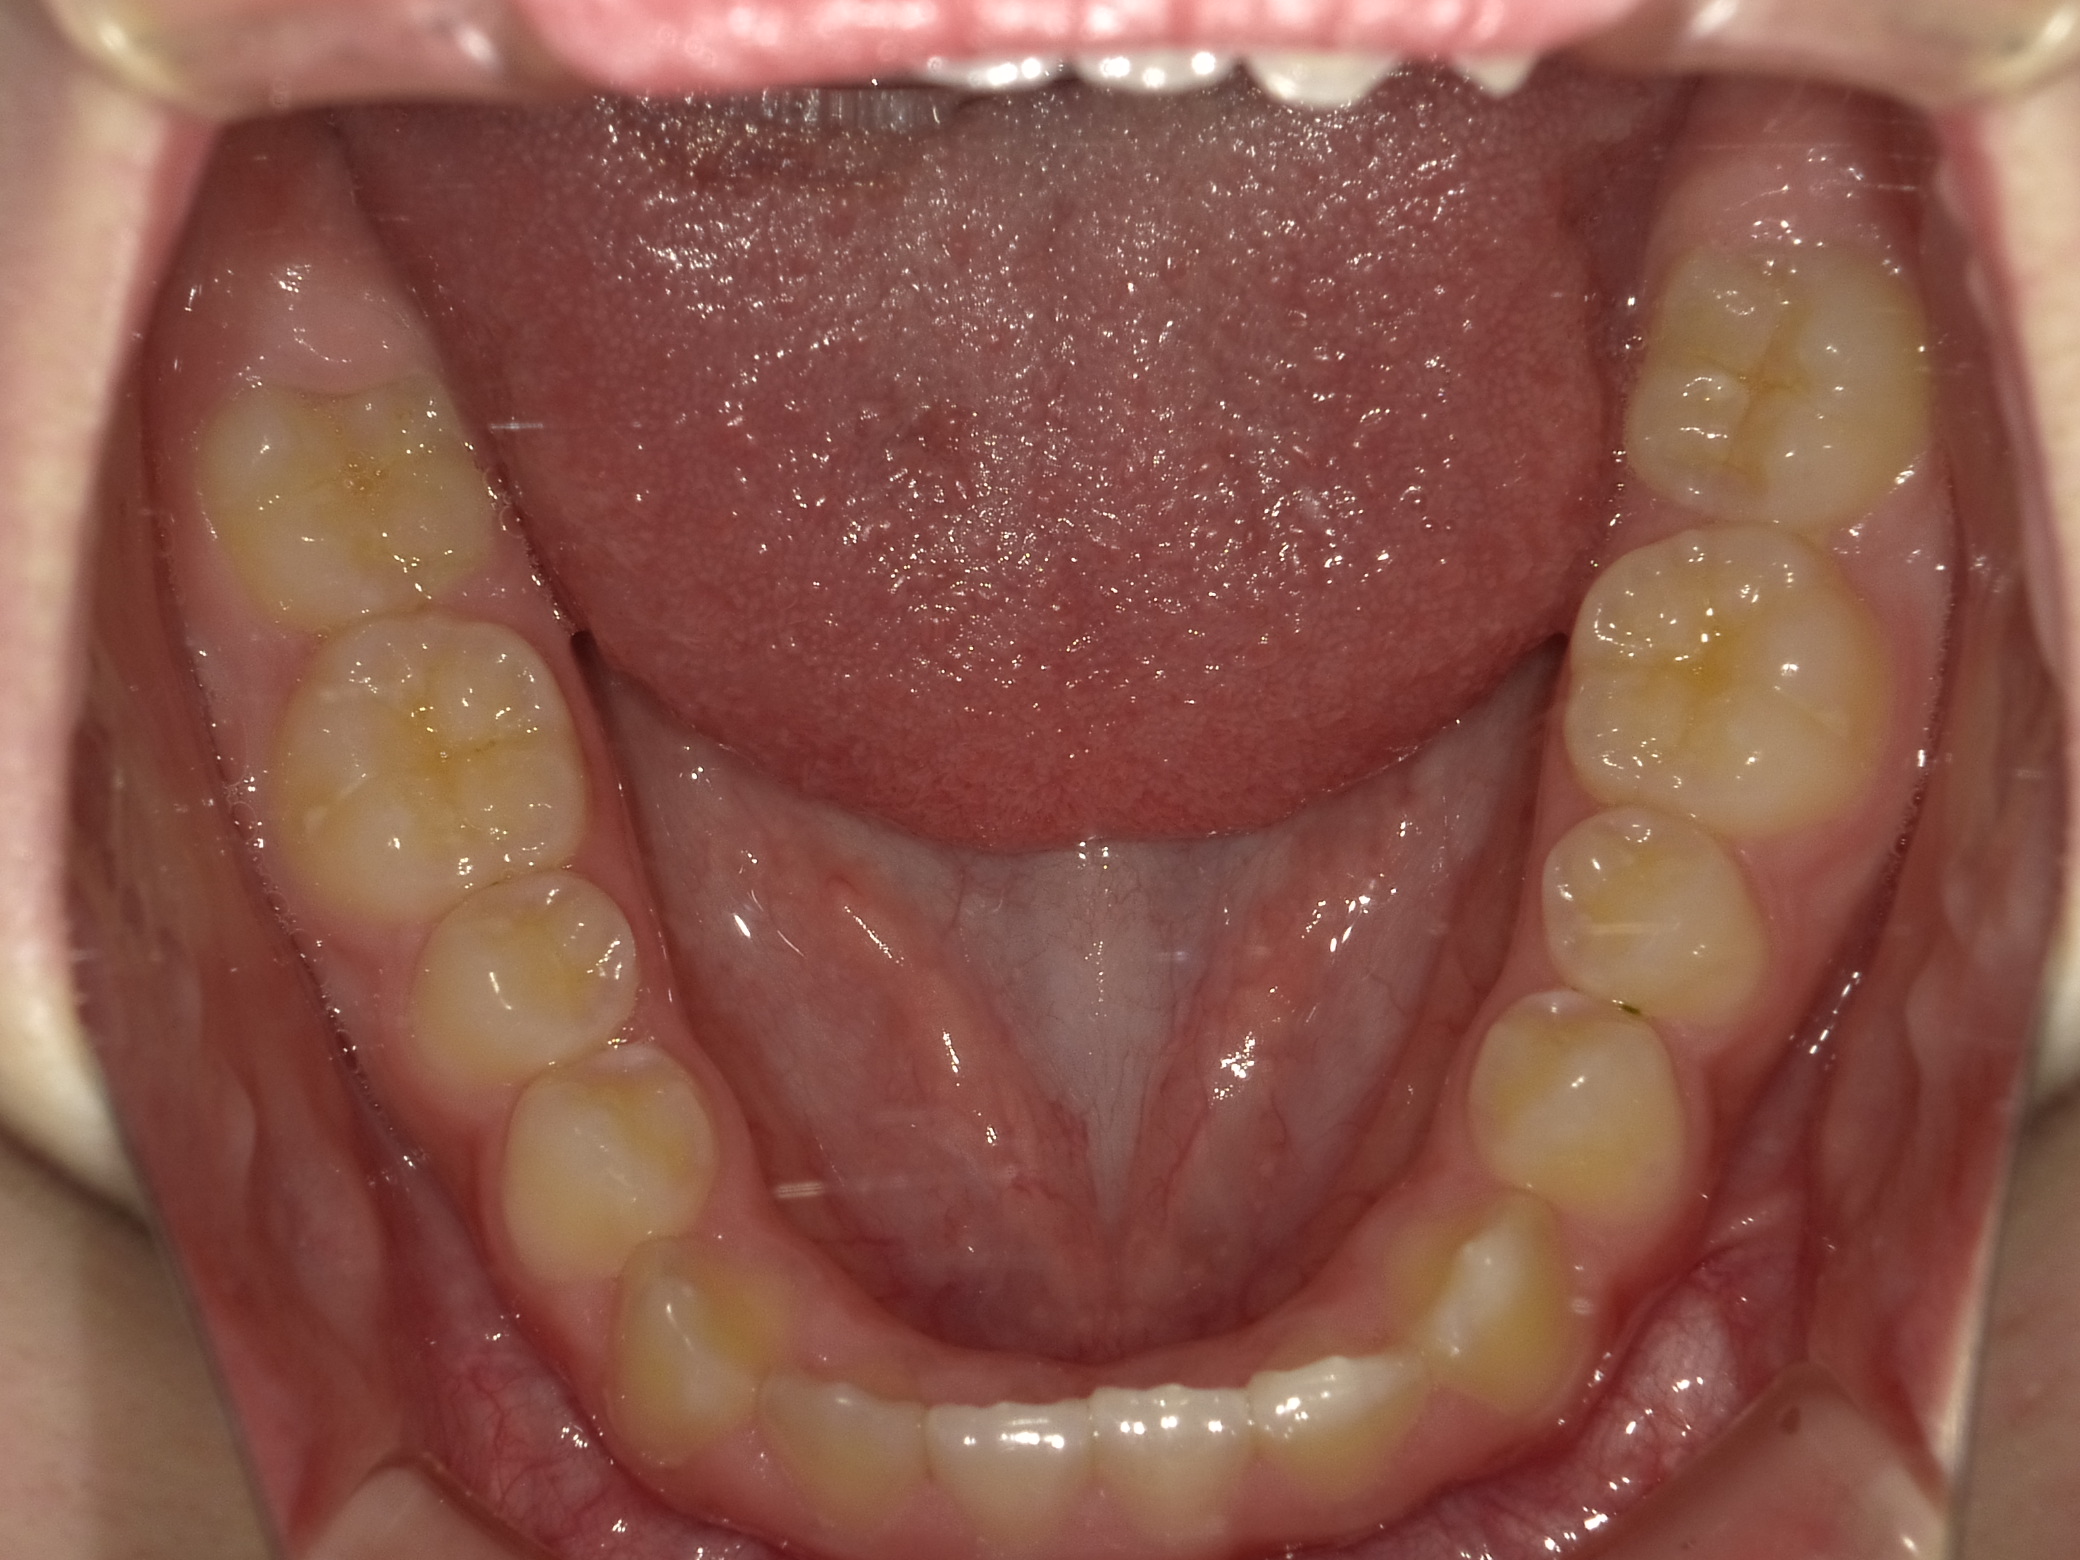

下顎